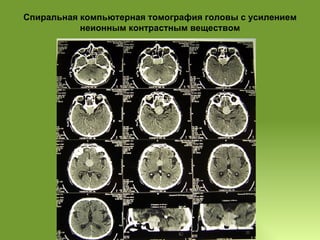

Спиральная компьютерная томография головы с усилением неионным контрастным веществом 26.09.2007  При СКТ определяется объёмное образование 45х37х32 мм однородной плотности  (45-48 HU), располагающееся интра- суб- и супраселлярно, занимающее 1\3 основной пазухи, которое доходит до нижних отделов боковых желудочков, с ровными чёткими контурами. После введения контрастного вещества плотность образования не повысилась. III желудочек расширен до 10-11 мм, боковые желудочки также умеренно расширены, симметричны, срединные структуры мозга не смещены. Субарахноидальное пространство головного мозга равномерно расширено. Заключение:  КТ-картина объёмного образования хиазмально-селлярной области, вероятнее всего- аденома гипофиза. Диффузные атрофические изменения ткани головного мозга.

Спиральная компьютерная томографияголовы с усилением неионным контрастным веществом 26.09.2007 При СКТ определяется объёмное образование 45х37х32 мм однородной плотности (45-48 HU), располагающееся интра- суб- и супраселлярно, занимающее 1\3 основной пазухи, которое доходит до нижних отделов боковых желудочков, с ровными чёткими контурами. После введения контрастного вещества плотность образования не повысилась. III желудочек расширен до 10-11 мм, боковые желудочки также умеренно расширены, симметричны, срединные структуры мозга не смещены. Субарахноидальное пространство головного мозга равномерно расширено. Заключение: КТ-картина объёмного образования хиазмально-селлярной области, вероятнее всего- аденома гипофиза. Диффузные атрофические изменения ткани головного мозга.